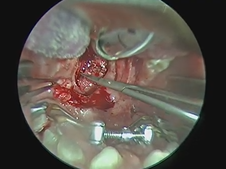

Microdirect Laryngoscopy with CO2 Laser Wedge Excisions for Subglottic Stenosis

- Date : 01/01/2020